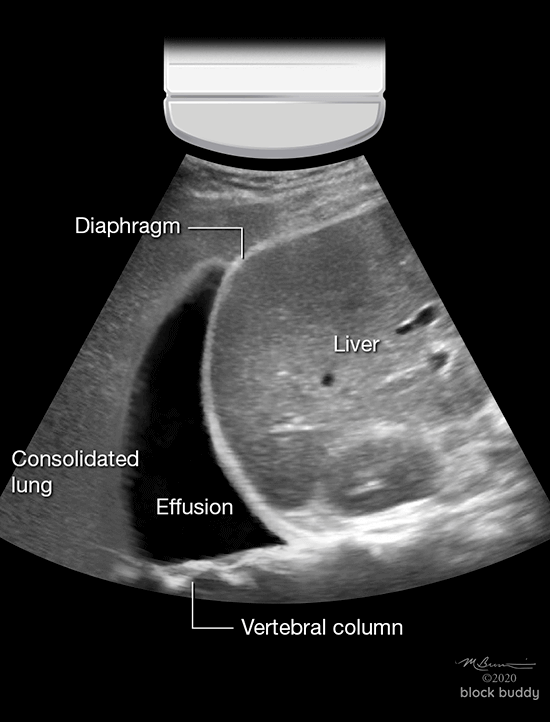

Pleural Effusion

- Accumulation of fluid within the pleural space.

- Commonly occurs with congestive heart failure, infections (pneumonia), renal failure, malignancy, and cirrhosis.

- Ultrasound can detect as little as 5ml of pleural fluid, and is more sensitive, specific, and accurate than chest x-ray.

- Ultrasound can also be used to assess pleural fluid volume and perform a thoracentesis.

- Estimate effusion volume using the following formula:

- Effusion volume (ml) = distance between pleura and diaphragm (mm) x 20

- Scanning can be performed in the supine position with the head of bed elevated, allowing fluid to collect in the dependent area of the lower thorax above the diaphragm.

- The transducer is placed in the long axis of zone 4, at the level of the diaphragm, near the mid or posterior axillary line.

- In the presence of a pleural effusion, an anechoic collection of fluid will appear superior to the diaphragm.

- The lung will appear consolidated from pleural fluid compression.

- The spine sign can be viewed posterior to the pleural effusion (superior to the diaphragm) since fluid can transmit ultrasound waves to the vertebral column.